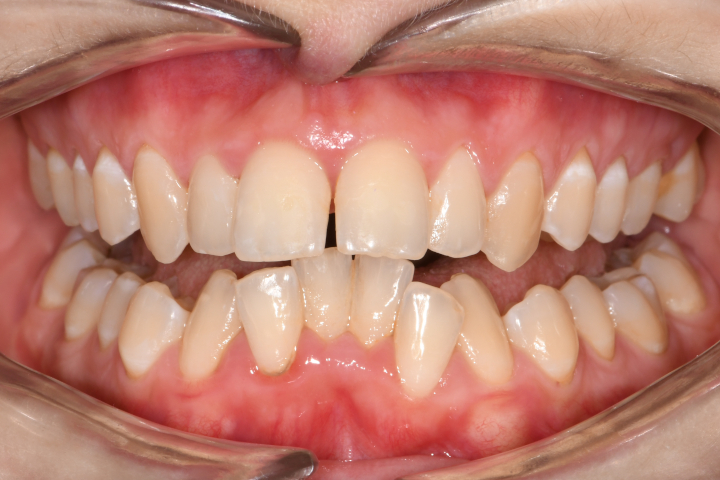

Az elmúlt évekből rengeteg szakmai referenciát tudnánk bemutatni, amelyek különböző fogszabályozási problémákat oldottak meg. Válogatva a több száz esetből, ezen az oldalon olyan képeket, információkat igyekeztünk bemutatni, amelyeknek a segítségével a jövőbeni pácienseinknek azt tudjuk üzenni: A Te fogsorod is lehet gyönyörű!

(Képeket a Pácienseink külön írásos beleegyezésével mutatjuk be!)